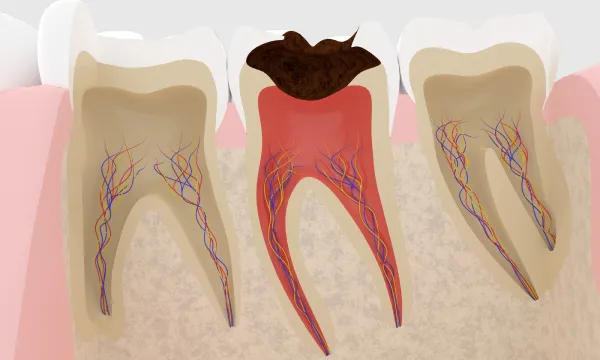

痛みが有る無しにかかわらずう蝕がある場合は、基本的には治癒することがないので欠損が生じます。 う蝕治療には、

1.細菌によって溶けるのを止める方法

う蝕治療では、細菌がいなくなるまで歯質を取り除いていく必要があります。取り切ると神経まで穴が開いてしまう疑いがある場合は、あえてう蝕を残して特殊な抗生剤と歯質保護薬剤を使用して1年弱待ちます。その後、神経表面に歯質が厚くなるのを待って、取り残したう蝕を取り切ります。 こうして、う蝕をとったら樹脂で歯質をコーティングし、失った歯質を補填します。この状態で次回までに痛まないか確認します。これは、削り取る刺激で神経に炎症が起きるからです。少ししみることはありますが、尾を引かないようならば神経は残せると判断します。

「神経をとりますね。」この言葉、驚きませんか?いくらひどい腰痛でも神経をとって治すことはしません。なぜ歯科だけに神経をとる治療があるのでしょうか?その答えは「歯の中」という特殊な環境にあります。 基本的には歯の中の神経以外の部分には血管はありません。 つまり新陳代謝が行われているのは神経のみ、ほかの部分は変化しない部分と言えます。 この神経の中の血管は非常に細く、虫歯などで炎症がおこると充血して血行不良になり容易に死んでしまうのです。 根の治療とは、死んだ組織、または回復が望めないほど炎症がある神経を取り除き、周りに広がった炎症の原因になる 腐敗物をきれいにして、炎症が起きづらい様に、空いた空間に無菌的にゴムを詰め込む治療のことです。